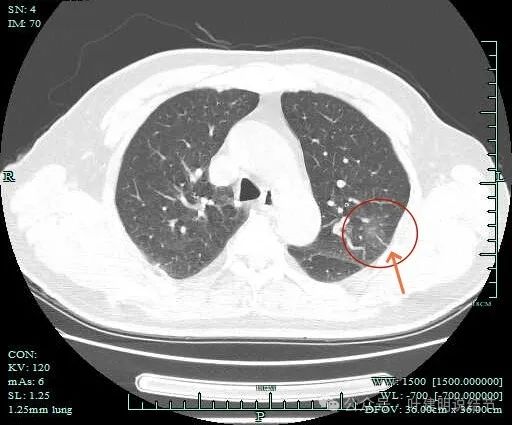

密度不纯,有少许偏实性成分出现,边缘毛刺明显,感觉病灶有一定收缩力。

混合密度,轻微胸膜牵拉,边缘细毛刺,灶内质不均,表面有浅分叶。

灶内有血管穿行或新生血管的样子,边缘细毛刺明显。

血管进入明显,且灶内端略粗于近心端。病灶内部也有血管穿行。

附近另有血管发出分支进入病灶。